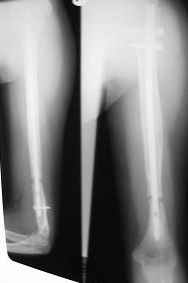

Uvazhaemye kollegy,Vashemu vnimaniyu predstavlaetsa nesroshiysya perelom plechevoi kosty v nizney treti, fiksirovan by interlocking nail, dve popitky "bone marrow" injections v techenii 2-h let bez rezultata, gde oshibka i kak luche postupit' s perelomom s takoi nastojiashei kartinoi , esli znat', chto on bil' osloznenim nevritom posle pervoi operasii (jatrogenic). SpasiboDr. Castro

Снимки не очень качественные (лучше снимать перпендикулярно поврехности, а не наискось, ну и разрешение можно было и побольше сделать). По тому, что видно - похоже, гвоздь заперт статически, есть диастаз, фиксатор вроде цел? Анализировать ошибки вряд ли можно, не зная, что было исходно, как делали синтез и какая картина была сразу после операции. Разве что напомнить о целесообразности динамизации, особенно при отсутствии динамики сращения через 2-3 мес.

При наличии диастаза не знаю, насколько есть смысл в инъекциях костного мозга. Судя по результату - толку не было. Видимо, сейчас лучше этот гвоздь удалить, пока не сломался по отверстию. Если есть возможность - рассверлить канал и ввести гвоздь большего диаметра, чтобы он подальше прошел в дистальный отломок, сколотить отломки и сделать или компрессионный остеосинтез, или хотя бы запереть гвоздь только динамически, рекомендовав больному опираться на руку.

Если нет возможности интрамедуллярного реостеосинтеза - удалить винты из центрального отломка, наложить аппарат и сдавить фрагменты.

Da fixator sely, distalny locking screw polomanny, nevrita Radial nerva seachas net, osteosyntez delalsa otkrito, diastaz okolo 1cm., nidavno boly nachili bespokoet. Da, est' vozmoznost' sdelat' close re-naling s rassverlivaniem kostno-mozgovogo kanala. Kak vi dumaete, nuzno li sdelat' kostnio plastiku iz malogo razreza v zone pereloma posle re-nailing?

Хорошо бы уменьшить диастаз. Какой гвоздь планируется использовать? У многих есть возможность использовать компрессирующее устройство. Можно после введения гвоздя и дистальных винтов наложить аппарат или интраоперационно, или на несколько дней, дать компрессию, а потом ввести проксимальный locking screw. Возможно, стоило бы немного изогнуть гвоздь перед введением, чтобы увеличить рекурвацию плеча.

Впрочем, это лучше уточнить по более качественным снимкам. Успехов. Держите нас в курсе событий.